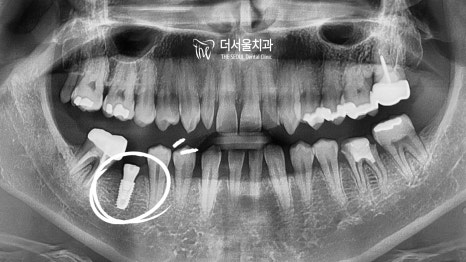

도대체 어떤 일로 오셨을까 공휴일 치과 에서 확인을 해보니!

왼쪽 아래 어금니가 깨져있었습니다.

꽤 오랜 시간 방치를 하셨던 것 같네요.

환자께서는 깨진 곳과 더불어

이미 빠진 채로 남아있는 곳이 있었습니다.

따라서 깨진 곳은 지르코니아 크라운으로,

상실된 곳은 디지털 임플란트를 통해

개선을 돕는 것으로 계획을 세웠습니다.

컴퓨터 분석을 통한 치료 계획을 세웠습니다.

이렇게 정확히 계산된 계획을 토대로

본격적인 식립 과정에 들어갔습니다.